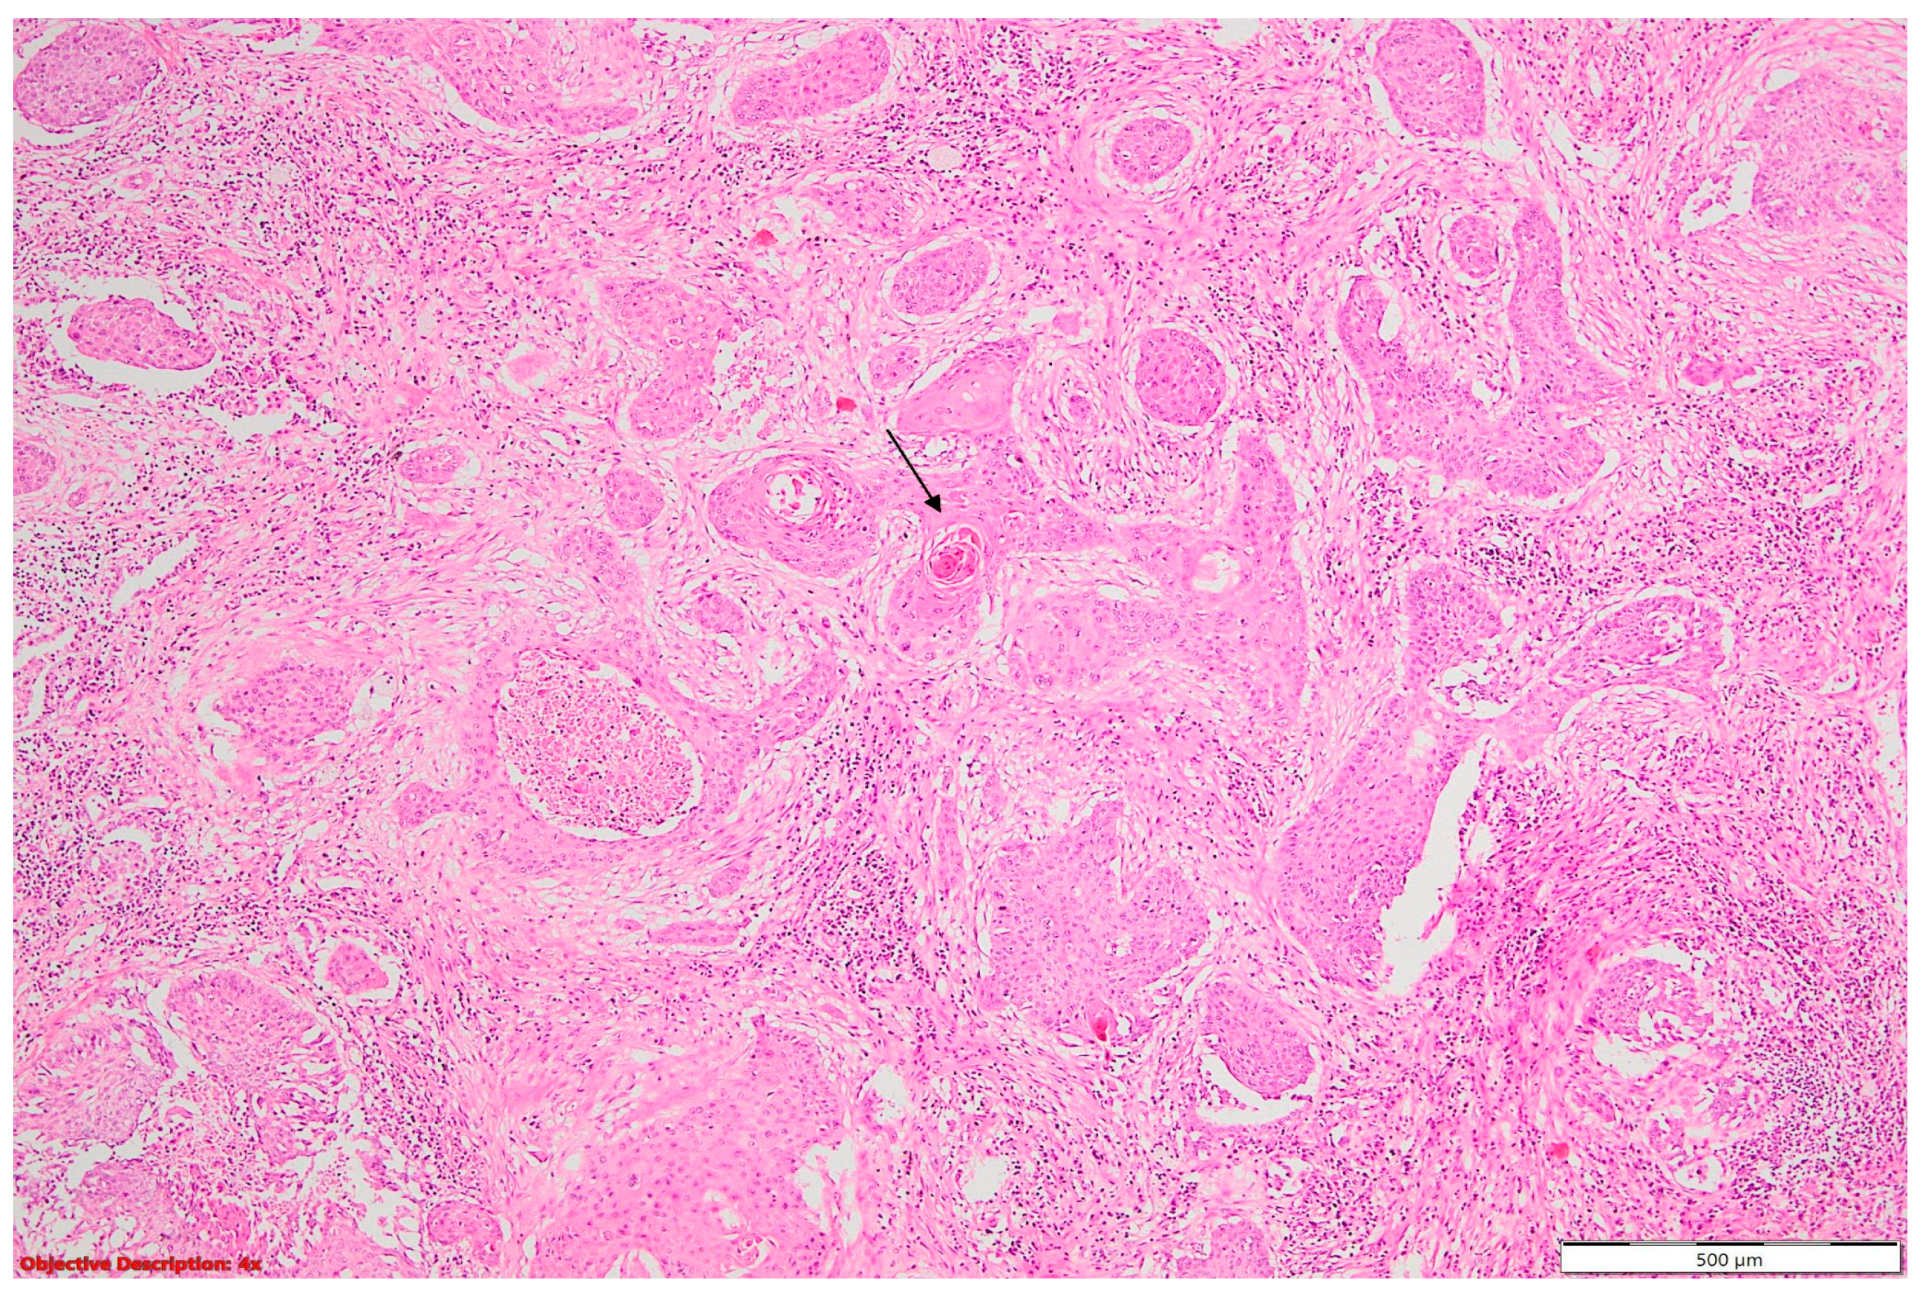

When examining the localization of coexisting lesions, a fascinating pattern emerged: a majority of cases (43%) showcased lesions within the same lobe (N = 16) (Figure 10). This intriguing observation raises questions about the accuracy of tumor staging, as lesions within the same lobe may suggest T3 tumor extension, potentially leading to misclassification and subsequent treatment decisions. Furthermore, 27% of cases exhibited lesions concurrently in both the same lobe and lymph nodes. This finding underscores the complexity of lesion distribution and highlights the need for meticulous nodal staging to accurately assess disease spread. In comparison, an additional 27% presented coexisting lesions spanning across different lobes (N = 10), posing challenges in determining the extent of tumor involvement and guiding surgical resection boundaries. Remarkably, only one case featured multiple lesions dispersed across distinct lung lobes and lymph nodes, underscoring the rarity and diagnostic dilemma posed by such multifocal presentations. These findings underscore the importance of the careful consideration of lesion localization in NSCLC staging to minimize staging errors, inform treatment decisions, and improve patient outcomes.

Figure 10.

Coexisting lesions: lung carcinoma (→) and fibronodular lesion (→); HE, 40×.